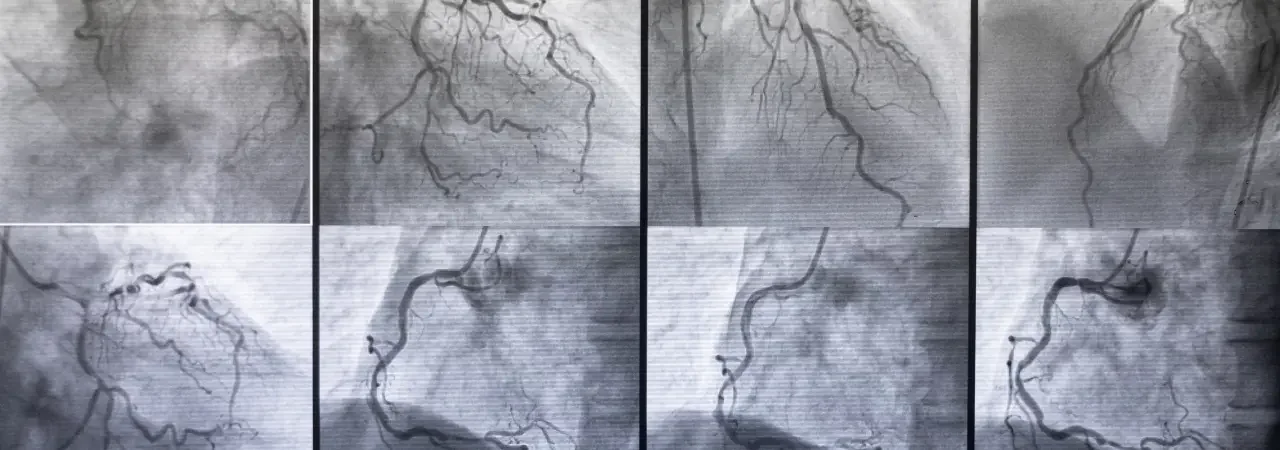

Önce çoklu set kan kültürü alır, ardından TTE ile başlar, TEE ile ve gerekirse BT-PET ile vejetasyon, abse, fistül ve protez gevşemesini doğrularız. Böylelikle, emboli riski yüksek vejetasyonları, iletim bozukluğu yapan abseleri ve gizli odakları görünür kılar, karar ağacını hızla çalıştırırız. Ayrıca, böbrek fonksiyonu, beslenme durumu ve antimikrobiyal duyarlılık verilerini eşleştiririz.